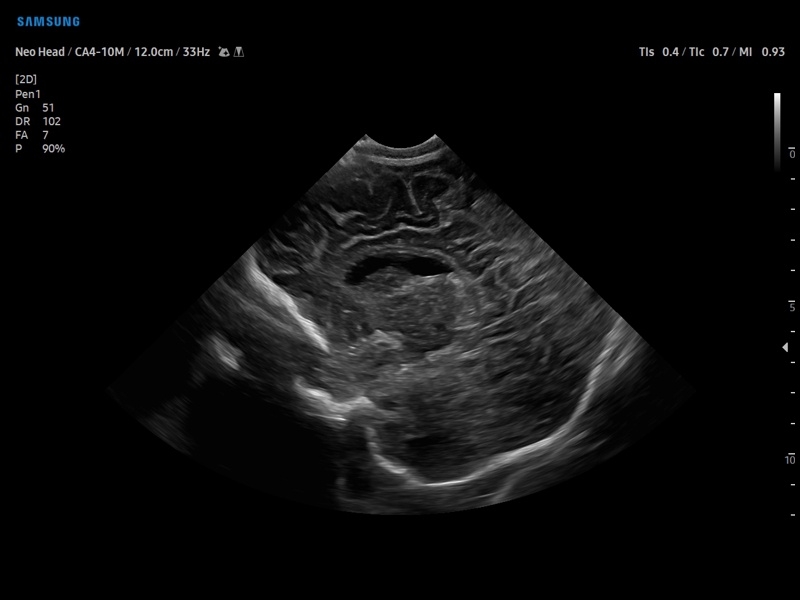

УЗИ-аппарат

Samsung Medison V8

Ультразвуковой сканер V8-RUS является экспертным классом (премиальный уровень) и производится компанией Samsung Medison. Сканер V8 обеспечивает превосходное качество изображения благодаря использованию технологии Crystal Architecture™, которая включает в себя передовое аппаратное обеспечение, монокристальную технологию изготовления датчиков и сложную программную обработку ультразвуковых лучей.

Samsung Medison V8 представляет собой современную ультразвуковую систему, в которой воплощен многолетний опыт компании Samsung в создании эргономичного и интеллектуального диагностического оборудования. Система оснащена передовыми инструментами автоматизации, которые значительно упрощают рабочий процесс и повышают эффективность исследований.